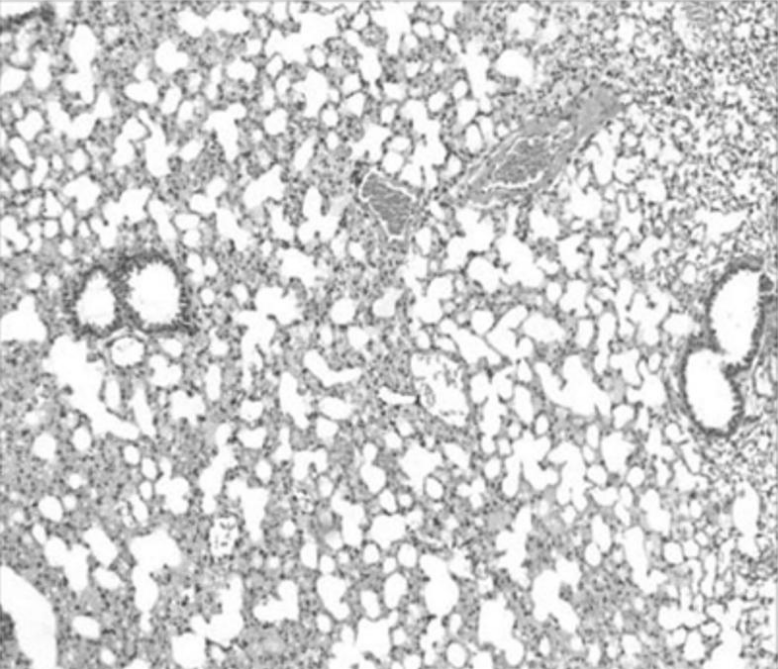

一种食管胃结合部平滑肌细胞的组织块法原代培养及鉴定方法

河北医科大学第四医院